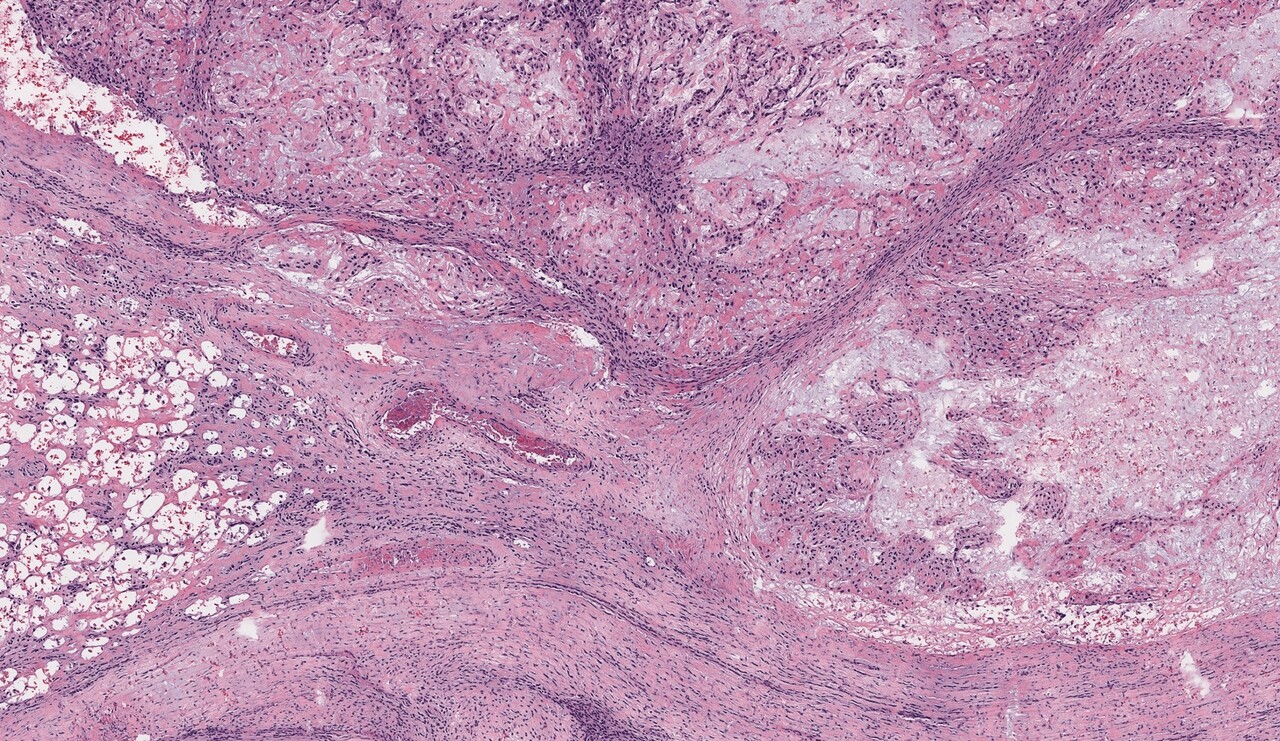

After we got some histology-like images of bone specimens, we showed the results to several pathologists and asked them if they could make diagnostic decisions using our grayscale UV-PAM images. Although they can identify the tumor and differentiate normal areas and tumor areas in the grayscale UV-PAM images, the color difference makes this process not as easy as conventional H&E images since the pathologists are used to the H&E color. Thus, we decided to use deep learning techniques to virtually stain our images to better match the conventional H&E slides, which will be more interpretable for pathologists. For this purpose, we chose the cycle-consistent generative adversarial network (i.e., CycleGAN) for unsupervised deep learning, which has shown superior performance in image processing and color conversion3. With this virtual staining technique and pre-trained neural network, we can generate H&E-like images for rapid intraoperative pathological diagnosis (Figure. 1) within minutes.

Figure 1. The workflow for PA histology and conventional H&E staining histology of bone samples.